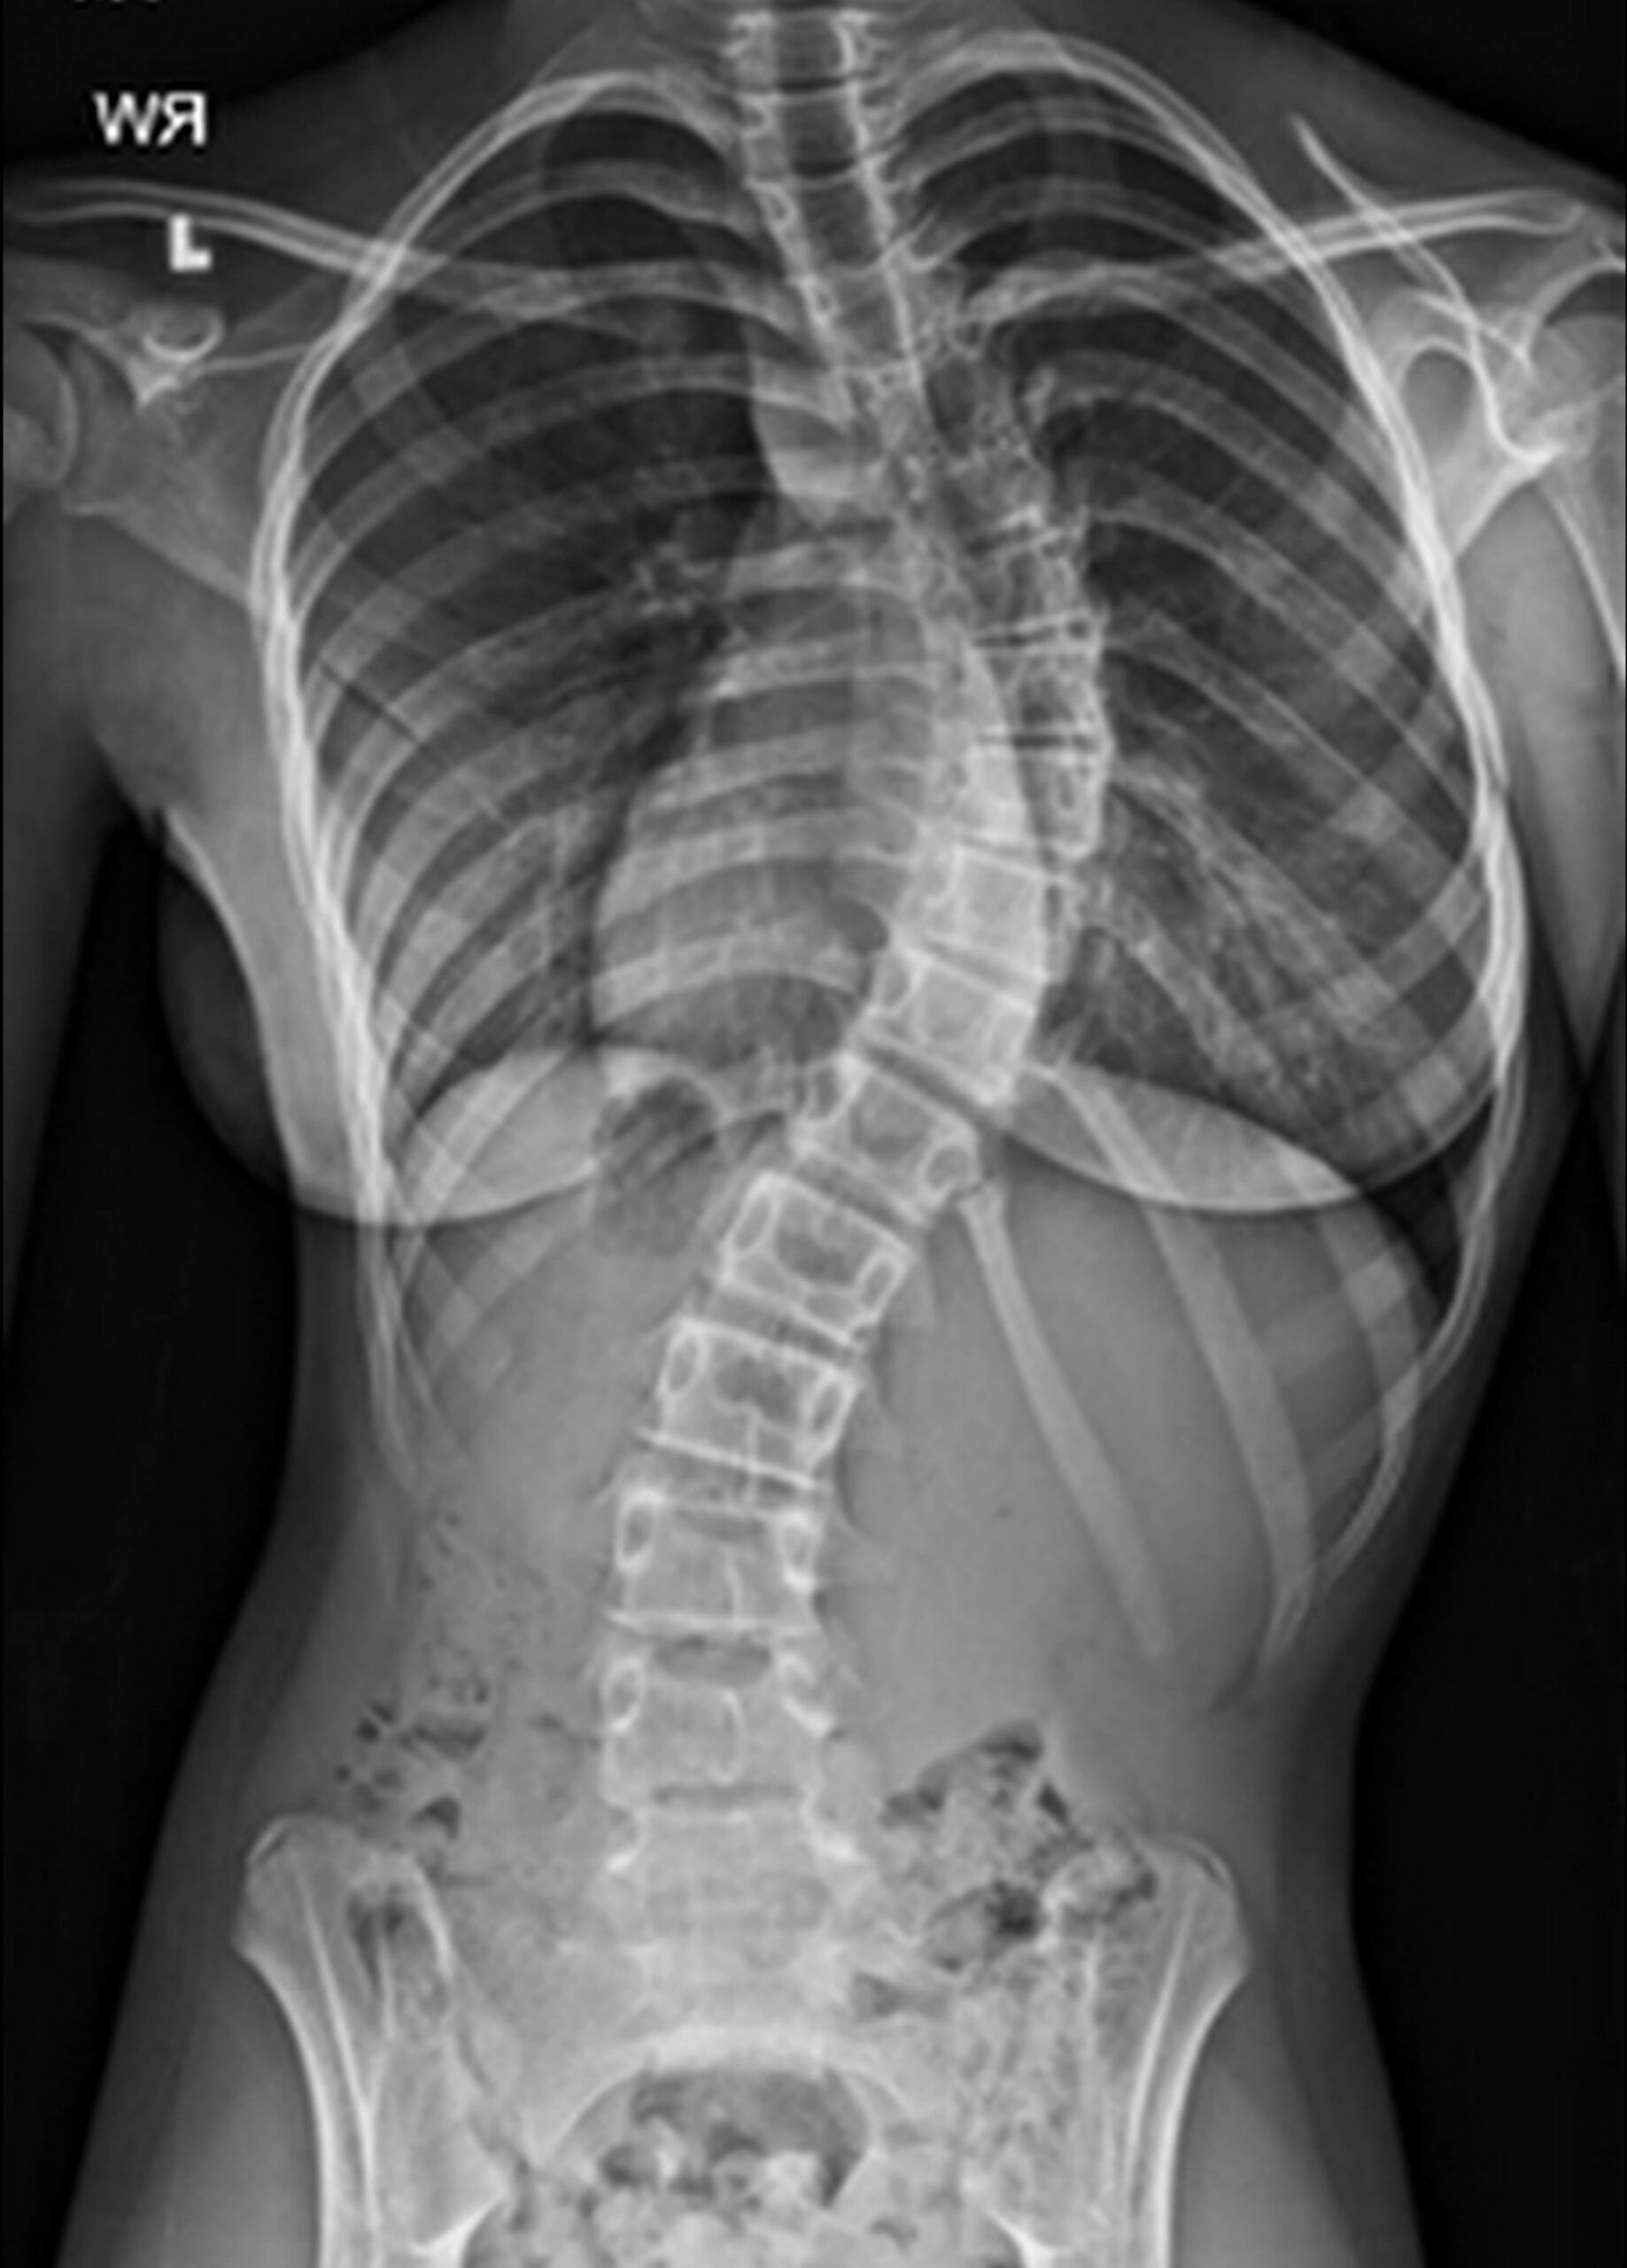

Eine Skoliose definiert sich über eine seitliche Verkrümmung der Wirbelsäule. Daraus entsteht eine komplexe dreidimensionale Veränderung.

Eine Skoliose wurde von der Scoliosis Research Society definiert als Seitverbiegung der Wirbelsäule von mehr als 10° Cobb-Winke

- Die Diagnose lässt sich mit einem Röntgen in Frontalebene bestätigen. Dabei kann auch der Schweregrad (Cobb-Winkel) ausgemessen werden.

Skoliose ist eine seitliche Verkrümmung der Wirbelsäule, die eine C- oder S-förmige Krümmung verursachen kann. Diese Verformung kann in verschiedenen Graden auftreten und betrifft oft Kinder und Jugendliche.

Skoliose wird in der Regel durch körperliche Untersuchungen und Röntgenaufnahmen der Wirbelsäule diagnostiziert. Die Diagnose erfolgt oft im Rahmen von Vorsorgeuntersuchungen bei Kindern und Jugendlichen.